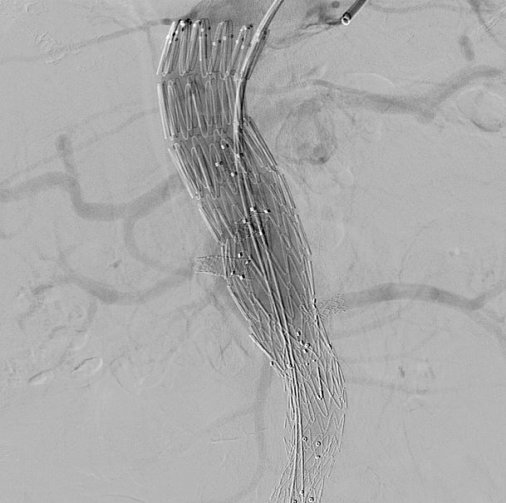

Σχεδιάστηκε ειδικό κατά παραγγελία μόσχευμα για το συγκεκριμένο ασθενή (custom made fenestrated stent graft) και η ελάχιστα επεμβατική αντιμετώπιση (από 3 μικροσκοπικές τομές), υπό ακτινοσκόπηση πραγματοποιήθηκε με τη συνεργασία του ειδικού τμήματος για τις συγκεκριμένες παθήσεις που λειτουργεί στο Mediterraneo.

Η θυριδωτή μέθοδος εφαρμόζεται εδώ και δύο χρόνια στο Mediterraneo Hospital και αποτελεί ελάχιστα επεμβατική μέθοδο αντιμετώπισης των θωρακοκοιλιακών και παρανεφρικών ανευρυσμάτων της αορτής με χαμηλότερη νοσηρότητα και πολύ καλύτερα αποτελέσματα σε σύγκριση με την ανοικτή μέθοδο αποκατάστασης των δύσκολων αυτών ανευρυσμάτων.